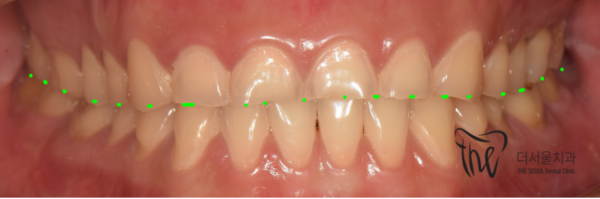

이 환자분은 치아가 거의 마모되어서 치과를 찾아오셨는데요.

보이시면 명백하게 이갈이로 인해 치아가 많이 손상된 것을 확인할 수 있습니다.

이렇게 심각하게 치아가 마모되는 것 자체로도 충분히 큰 문제이지만

이갈이를 할때 평소 이성적인 상황에서는 생각할 수 없을정도로

큰 힘으로 치아에 힘을 가하기 때문에 턱관절에도 문제를 일으키고

편두통까지 생길 수 있어 아주 다양한 합병증의 원인이 될 수도 있습니다.

This patient came to the dentist because his teeth were almost worn out.

If you see it, you can clearly see that the teeth are damaged a lot by the grinding.

It's a big enough problem that your teeth are seriously worn out

When you brush your teeth, you can't think of it in a rational situation

It can cause problems in the jaw joint because it exerts a lot of strength on the teeth

Migraine headaches can occur, which can cause a wide variety of complications.